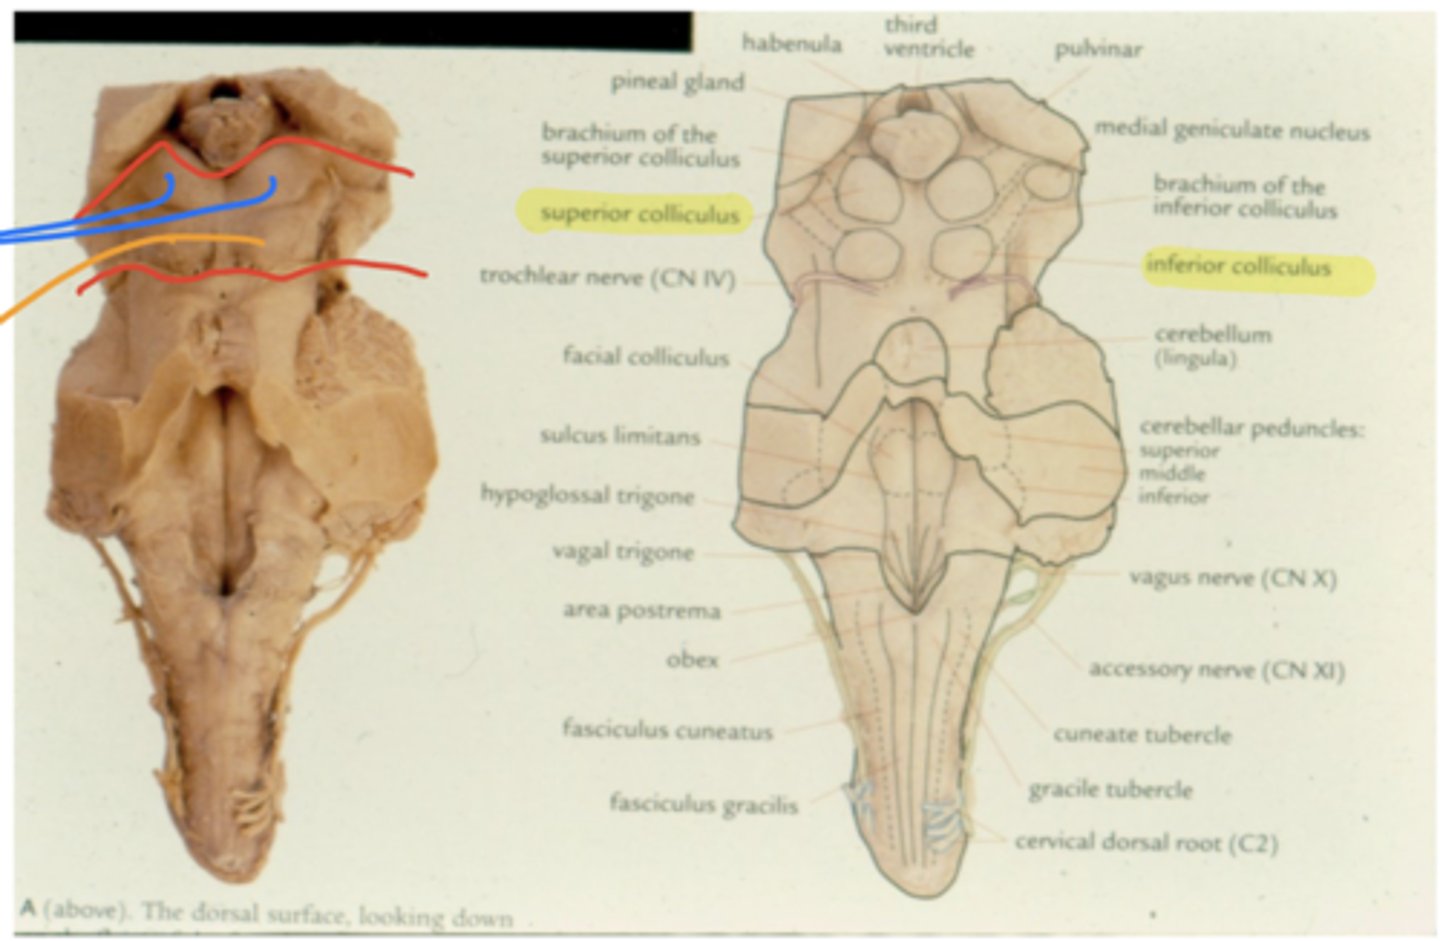

What notable structures are on the dorsal surface of the mesencephalon (tectum)?

1. superior colliculi (right and left)

2. inferior colliculi (right and left)

What other notable structure should you see if you see two red nuclei?

"if you see two red nuclei you're at the superior colliculus level"

Where does CN IV exit the brainstem?

inferior colliculus (dorsal surface)

exits dorsal + caudal (posteroinferior) to nucleus

What injuries usually cause IV nerve palsies?

acceleration/deceleration

why? -- location nerve exits the brain makes it susceptible to being crushed by posterior structure